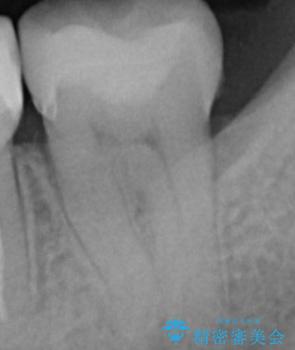

- 銀の詰め物を白くしたいとの事で来院。

銀の詰め物を外し、拡大鏡下でう蝕を全て取り除いたのを確認して

e-maxインレーにて治療しました。

セラミックの詰め物(e-maxインレー)は、銀の詰め物に比べて表面がツルツルしていて

表面の細菌が付着しにくいので、う蝕の再発リスクを下げる事ができます。